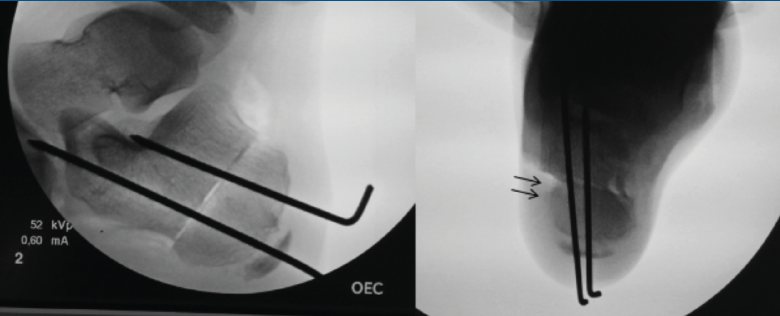

Técnica quirúrgica (Figura 13)

Figura 13. Osteotomía de deslizamiento medial del calcáneo. Escopia intraoperatoria lateral y axial de retropié donde se visualiza la osteotomía de deslizamiento medial del calcáneo.

La osteotomía es perpendicular a la cara lateral del calcáneo y oblicua hacia anterior desde el borde dorsal de la tuberosidad mayor hasta su borde plantar. Aunque clásicamente se realiza esta osteotomía de forma abierta, actualmente se puede realizar de forma percutánea. Mediante maniobra externa realizamos una medialización de al menos 1 cm, más osteosíntesis con AK o tornillos canulados de esponjosa(11).